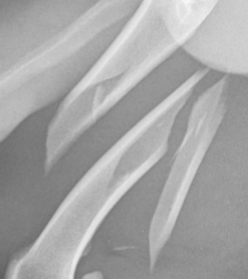

New cards

Montagia fracture

Fracture with accompanying luxation

<p>Fracture with accompanying luxation</p>